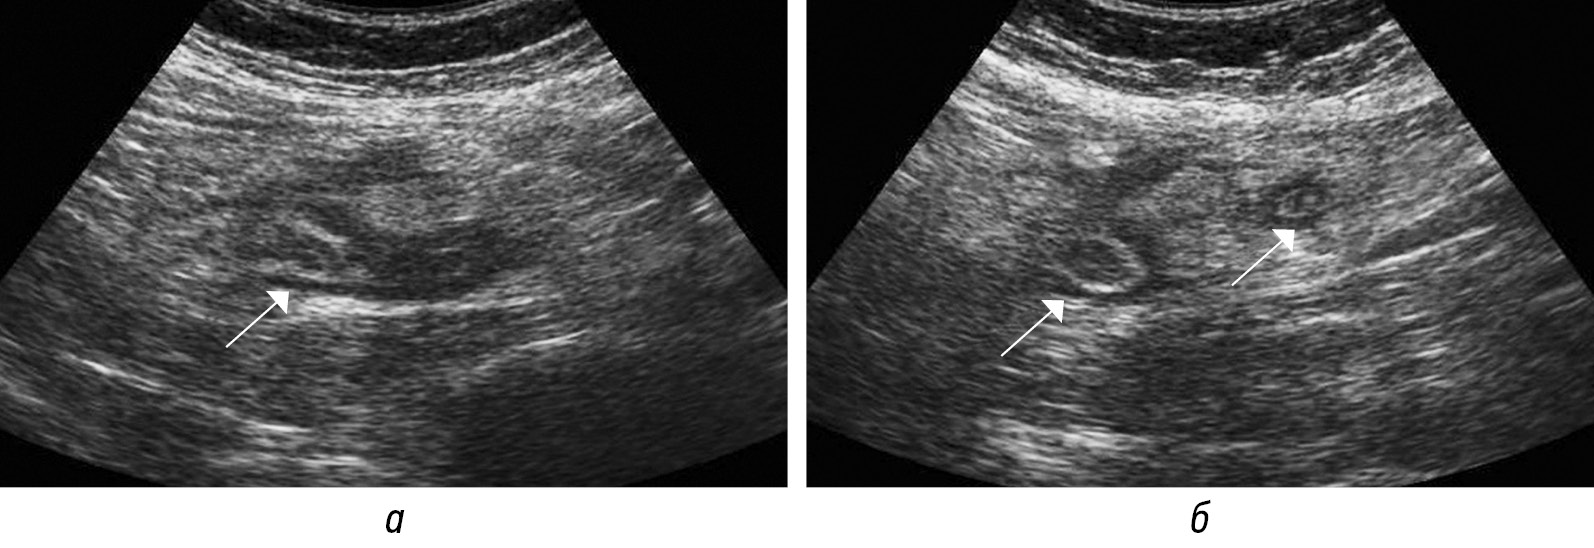

Рис. 3. Сонограммы воспаленного аппендикса (стрелки) в В-режиме по короткой (а) и длинной (б) осям

Fig. 3. Sonograms of the inflamed appendix (arrows) in B-mode on the short axis (а) and on the long axis (б)

Диаметр аппендикса суммарно представлен содержимым и стенками аппендикса. При нативной КТ не всегда удается дифференцировать стенки от содержимого, необходимо введение контрастного вещества (рис. 2), в то время как при высокочастотном УЗИ возможно дифференцировать слои стенки аппендикса, наиболее информативен срез по короткой оси отростка (рис. 3, а, б). Во всех источниках утолщением стенок аппендикса считается толщина более 2 мм. Только при УЗИ возможно определить несжимаемость при компрессии аппендикса, что является важным признаком острого воспаления [18].